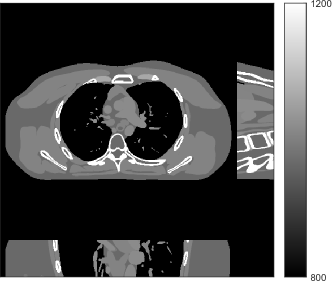

Refer to caption

Figure 1: Reconstruction targeted ROI of the true XCAT phantom displayed with central slices along the axial, sagittal and coronal directions. The display window is [800, 1200] HU.

We simulated 3D axial cone-beam scans using a 840×840×9684084096840\times 840\times 96 XCAT phantom with Δx=Δy=0.4883subscriptΔ𝑥subscriptΔ𝑦0.4883\Delta_{x}=\Delta_{y}=0.4883 mm and Δz=0.625subscriptΔ𝑧0.625\Delta_{z}=0.625 mm. We generated sinograms of size 888×64×98488864984888\times 64\times 984 using GE LightSpeed cone-beam geometry corresponding to a mono-energetic source with I0=1×104subscript𝐼01superscript104I_{0}={\color[rgb]{0,0,0}1\times}10^{4}, 5×1035superscript1035\times 10^{3}, 3×1033superscript1033\times 10^{3}, and 2×1032superscript103{2\times 10^{3}} incident photons per ray and no scatter, respectively. Tab. I shows percentages of non-positive measurements under different dose levels. We set these non-positive measurements to 1×1051superscript1051\times 10^{-5} for generating the post-log sinogram that PWLS-based methods rely on [13]. We reconstructed the 3D volume with a size of 420×420×9642042096420\times 420\times 96 at a coarser resolution of Δx=Δy=0.9766subscriptΔ𝑥subscriptΔ𝑦0.9766\Delta_{x}=\Delta_{y}=0.9766 mm and Δz=0.625subscriptΔ𝑧0.625\Delta_{z}=0.625 mm. The patch size during reconstruction was 8×8×88888\times 8\times 8 and the stride was 3×3×33333\times 3\times 3. For evaluating reconstruction performance, we chose an ROI that was composed of the central 64 out of 96 axial slices, and refer to it as the reconstruction targeted ROI. Fig. 1 shows the central slices of the true XCAT phantom inside this ROI along three directions. In the reconstruction stage of PWLS-ULTRA and SPULTRA, we used 4 iterations for the image update step, i.e., P=4𝑃4P=4, for a good trade-off between algorithms’ convergence and computational costs. We used 121212 ordered subsets, i.e., M=12𝑀12M=12, to speed up the algorithm. The initial image for the ULTRA methods was reconstructed by PWLS-EP, whose regularization parameter was set empirically to ensure good reconstruction quality as βep=213subscript𝛽𝑒𝑝superscript213\beta_{ep}=2^{13} for all the experimented dose cases. We used an analytical filtered back-projection (FBP) method FDK [59] to initialize PWLS-EP. The FDK images of XCAT phantom for all the dose levels are shown in the supplement. Due to the fact that SPULTRA has a similar cost function as PWLS-ULTRA in each outer iteration, we used the same parameter settings for both methods: β=4×104𝛽4superscript104\beta=4\times 10^{4} and γc=4×104subscript𝛾𝑐4superscript104\gamma_{c}=4\times 10^{-4}, which we observed worked well for all the dose levels we tested.